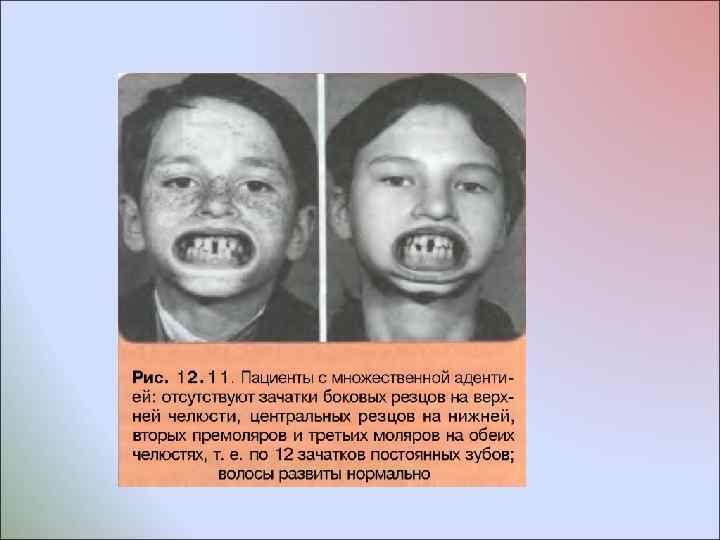

За рубежом отдельные авторы различают сле дующие варианты врожденного отсутствия зубов с учетом их количества: менее 6 зубов, более 6 зубов и полное отсутствие их зачатков. В период прикуса временных зубов отсутствие их зачатков называют гипо , олиго или анолактодентией; В период прикуса постоянных зубов - гипо , олиго или анодентией Такое многообразие терминов неудобно в практической работе и их применение не является точным, так как в периоде прикуса временных зубов важно в первую очередь учитывать, каких временных зубов нет, отсутствуют ли при этом зачатки постоянных зубов, какие именно и сколько; как отразилось отсутствие зубов на формировании зубочелюстной системы и лица; каков будет план комплексных лечебных мероприятий и в какой последовательности они будут применены; каков долгосрочный прогноз лечения. В периоде прикуса постоянных зубов важно учитывать, какие именно зачатки зубов отсутствуют; как расположены имеющиеся зубы и как они смыкаются в окклюзии; сколько сохранилось в зубных рядах временных зубов и каково состояние их корней; сочетается ли врожденное отсутствие отдельных или всех зубов с нарушением развития других производных эктодермы (волос, кожи, ногтей, хрусталика глаза, слизистых оболочек) или нет; каков будет план комплексных лечебных мероприятий и в какой последовательности они будут применены; каков долгосрочный прогноз лечения

За рубежом отдельные авторы различают сле дующие варианты врожденного отсутствия зубов с учетом их количества: менее 6 зубов, более 6 зубов и полное отсутствие их зачатков. В период прикуса временных зубов отсутствие их зачатков называют гипо , олиго или анолактодентией; В период прикуса постоянных зубов - гипо , олиго или анодентией Такое многообразие терминов неудобно в практической работе и их применение не является точным, так как в периоде прикуса временных зубов важно в первую очередь учитывать, каких временных зубов нет, отсутствуют ли при этом зачатки постоянных зубов, какие именно и сколько; как отразилось отсутствие зубов на формировании зубочелюстной системы и лица; каков будет план комплексных лечебных мероприятий и в какой последовательности они будут применены; каков долгосрочный прогноз лечения. В периоде прикуса постоянных зубов важно учитывать, какие именно зачатки зубов отсутствуют; как расположены имеющиеся зубы и как они смыкаются в окклюзии; сколько сохранилось в зубных рядах временных зубов и каково состояние их корней; сочетается ли врожденное отсутствие отдельных или всех зубов с нарушением развития других производных эктодермы (волос, кожи, ногтей, хрусталика глаза, слизистых оболочек) или нет; каков будет план комплексных лечебных мероприятий и в какой последовательности они будут применены; каков долгосрочный прогноз лечения

Врожденное отсутствие до 10 постоянных зубов Зубной ряд, в котором отсутствуют отдельные зубы, обычно недоразвит, между зубами имеются тремы, передние зубы противостоящего зубного ряда располагаются тесно, высота нижней части лица уменьшена Адентия зачатков постоянных боковых резцов верхней челюсти. При адентии боковых резцов на верхней челюсти обычно наблюдается диастема, которая подлежит устранению путем мезиального перемещения центральных резцов. В отдельных случаях, чаще при адентии отдельных резцов на нижней челюсти и мезиальном наклоне зачатков клыков, стремятся установить постоянные клыки рядом с центральными резцами, если их бугры имеют округлую форму. По показаниям одновременно с ортодонтическим устранением диастемы перемещают клыки дистально, после чего замещают отсутствующие зубы путем протезирования

Врожденное отсутствие до 10 постоянных зубов Зубной ряд, в котором отсутствуют отдельные зубы, обычно недоразвит, между зубами имеются тремы, передние зубы противостоящего зубного ряда располагаются тесно, высота нижней части лица уменьшена Адентия зачатков постоянных боковых резцов верхней челюсти. При адентии боковых резцов на верхней челюсти обычно наблюдается диастема, которая подлежит устранению путем мезиального перемещения центральных резцов. В отдельных случаях, чаще при адентии отдельных резцов на нижней челюсти и мезиальном наклоне зачатков клыков, стремятся установить постоянные клыки рядом с центральными резцами, если их бугры имеют округлую форму. По показаниям одновременно с ортодонтическим устранением диастемы перемещают клыки дистально, после чего замещают отсутствующие зубы путем протезирования

Адентия вторых премоляров нередко сочетается с адентией боковых резцов верхней челюсти и третьих моляров одной или обеих челюстей. При такой патологии наблюдается недоразвитие той челюсти, на которой отсутствует наибольшее количество постоянных зубов

Адентия вторых премоляров нередко сочетается с адентией боковых резцов верхней челюсти и третьих моляров одной или обеих челюстей. При такой патологии наблюдается недоразвитие той челюсти, на которой отсутствует наибольшее количество постоянных зубов